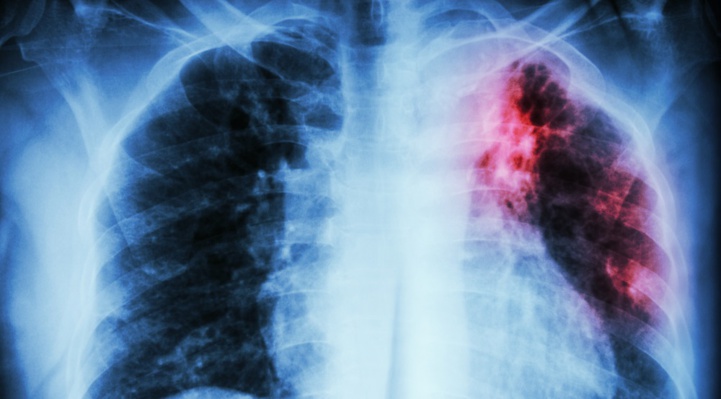

Il sied de rappeler que la tuberculose est une maladie infectieuse qui se transmet par voie aérienne. Elle atteint souvent les poumons, mais aussi d’autres organes. En cas d’absence ou de retard de traitement, elle peut être cause de décès.